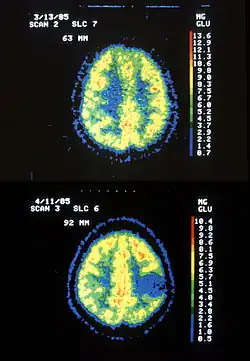

| Two PET images—the upper of which shows a normal brain and the lower shows astrocytoma | |

Astrocytoma is a type of brain tumor. Astrocytomas (also astrocytomata) originate from a specific kind of star-shaped glial cell in the cerebrum called an astrocyte. This type of tumor does not usually spread outside the brain and spinal cord, and it does not usually affect other organs. After glioblastomas, astrocytomas are the second most common glioma and can occur in most parts of the brain and occasionally in the spinal cord.[1]